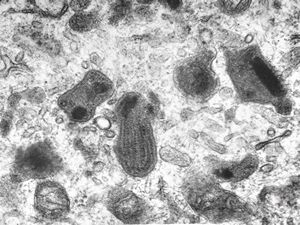

M, 62y. | mitosis … angiomatous tumor, v.s. Kaposi sarcoma

M, 62y. | angiomatous tumor, v.s. Kaposi sarcoma

M, 62y. | Weibel-Palade body - angiomatous tumor, v.s. Kaposi sarcoma